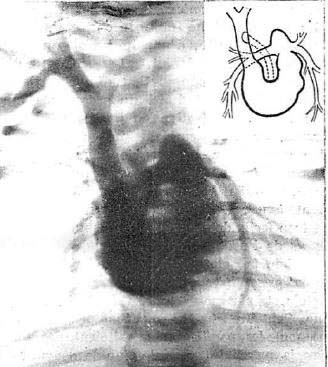

図2. カテーテル法によるイヌの心腔造影.自己人体実験では造影効果が得られず,失敗に終わった.

【要旨】 上肢静脈から造影剤を投与して上大静脈~心腔を造影することには誰も成功していない.そこで,前年に自分が報告した右心系へのカテーテル挿入法を拡張して造影を試みた.前報の後,22例にカテーテル挿入を試み,15例で成功した(図2).動物実験で心腔が造影されることを確認し,再び自己人体実験を試みた.

1回目は,左肘静脈から8Fの心臓カテーテルを挿入し,25%ヨウ化ナトリウム20ccを急速注入して撮影し,肺動脈の画像が得られたが心腔は見えなかった.注入後まもなく軽度のめまいがあったがすぐ消失した.1日半にわたってヨウ素による鼻閉感,味覚障害があった.2回目は,右大伏在静脈から8F尿管カテーテルを挿入し,Uroselectan(ウロセレクタン)を20cc注入したが,技術的な理由によりX線撮影はできなかった.

動物実験の観察では,心腔の形態は心房収縮期,心室収縮期,静止期の3時相が区別され,それぞれ形態が異なっている.

【解説】 右心系にカテーテルを挿入する前掲の第一報は予想に違わず大きな批判を受けたが,その続報として再び自らを実験台にして心腔造影を試みた論文である.動物実験では造影写真が得られたが,自己人体実験での撮影には失敗した.ここで述べられている自己人体実験は2回であるが,実際には9回行なってすべて失敗したらしい.論文の後半には,お茶を濁すように動物実験における心腔形態の観察結果が述べられている.この論文発表の直後,Forssmannは医学界から追放された.